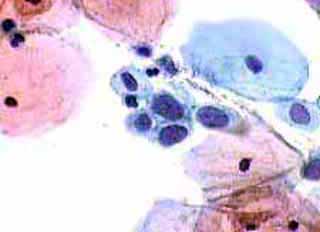

Ασυμπτωματική ασθενής 39 ετών. PH κόλπου 4,4. Κολποσκόπιση:

Στην δοκιμασία οξικού οξέως και στην δοκιμασία Lugol, αρνητική περιοχή, τόσο στο πρόσθιο, όσο και στο οπίσθιο χείλος του τραχήλου, σε ακτίνα 3-4 χιλ. και πλάτος περίπου 5 χιλ., με εικόνα διακριτικού επίπεδου μωσαϊκού.